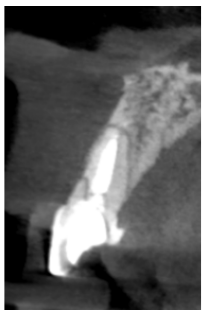

Se llevó a cabo una exploración radiológica que incluyó una radiografía periapical y la realización de un CBCT con el fin de conocer mejor la distribución de la fractura que presentaba el ICSI. (Figura 2). En la exploración radiográfica se confirma la presencia de una fractura oblicua que comprende la región del tercio medio radicular y se extiende en sentido corono-palatino hacia la región coronal. Así mismo, se puede observar la presencia de un tratamiento de conductos dentro de la normalidad y la ausencia de tabla vestibular en la región de los dos tercios coronales de la raíz del ICSI.

explorado en CBCT. Se puede apreciar una fractura cuya extensión compromete la estructura coronal y del primer tercio coronal del incisivo.